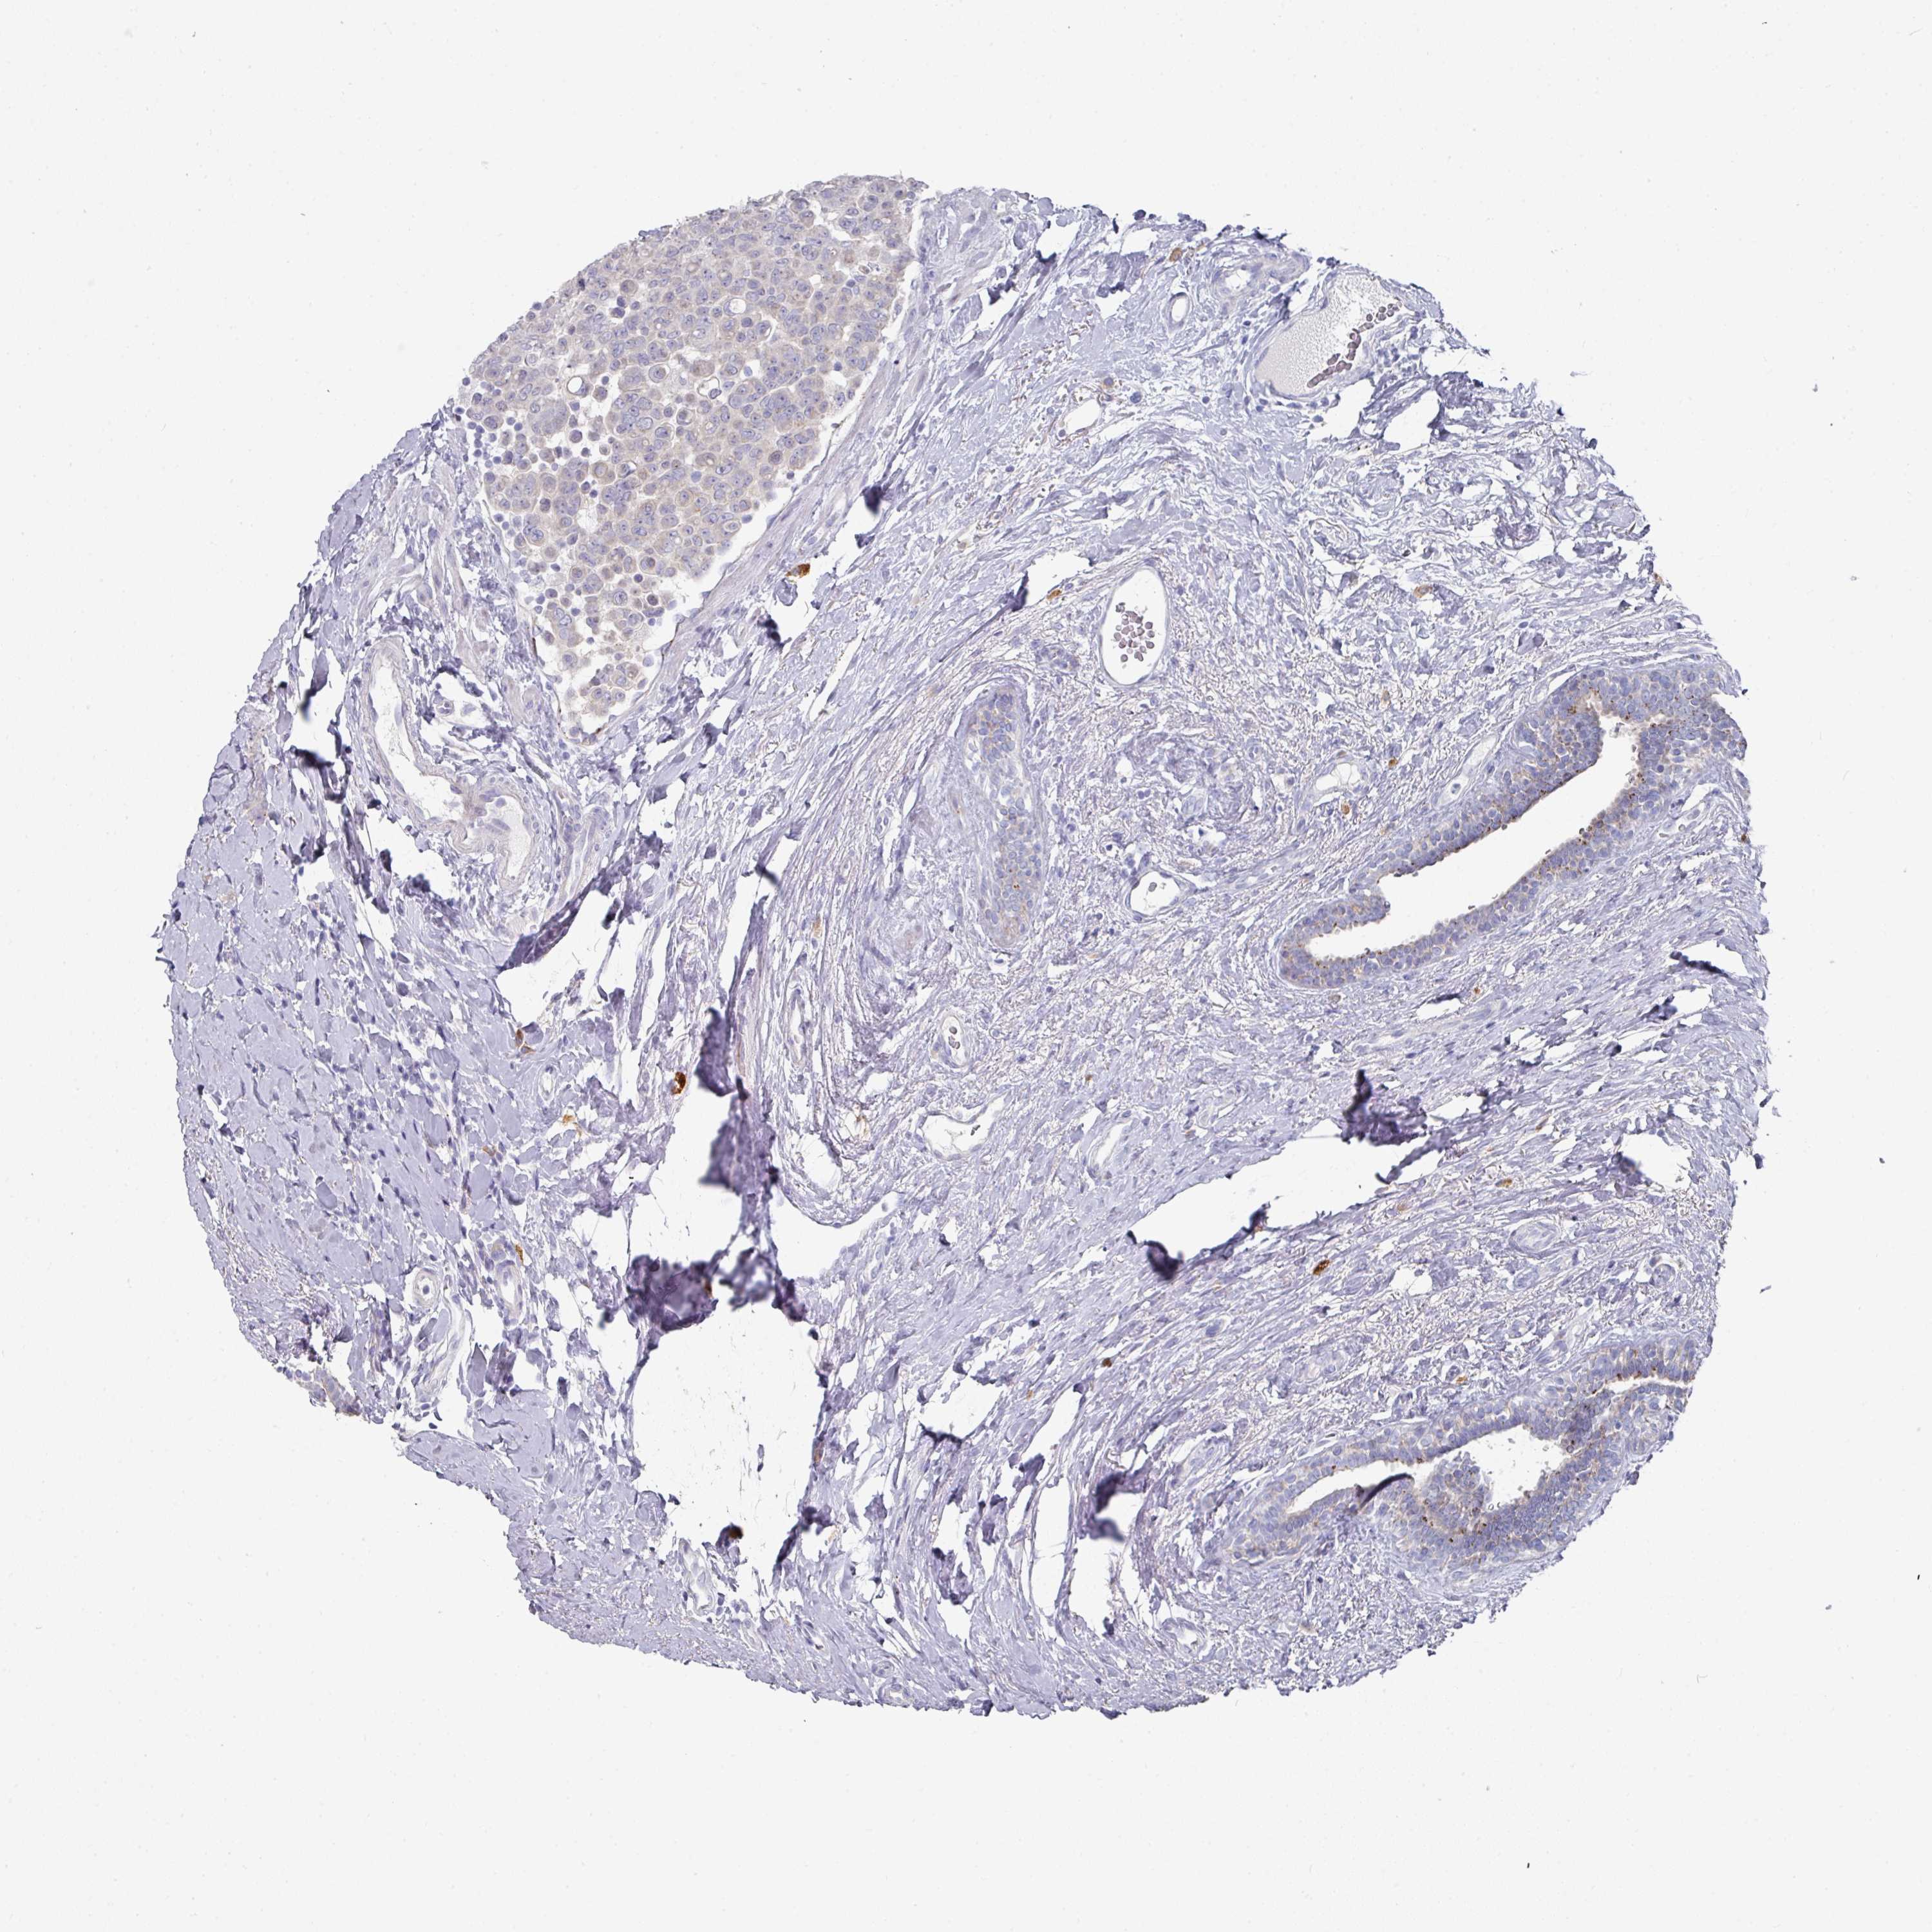

CANCER BREAST CANCER Show tissue menu

BRCA TCGA BRCA VALIDATION PROTEIN EXPRESSION